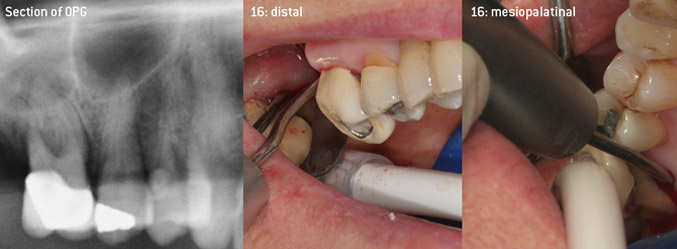

Come pionieri dello sviluppo della nuova punta per ablatori 3AP diamantata, i due dentisti hanno riconosciuto la necessità di migliorare le restrizioni di manipolazione delle punte diamantate disponibili in commercio, specialmente durante il trattamento della forcazione e lavorando su tasche intraossee strette. Tutto ciò deve essere fattibile sia per procedure non chirurgiche (figura 2) sia per procedure chirurgiche (figura 3).

debridement chiuso delle forcazioni sui denti 26 e 36

Fig. 2: debridement chiuso delle forcazioni sui denti 26 e 36 in caso di una perdita avanzata di attacchi

(Foto (figure 2-4): © Dott. Christian Graetz)